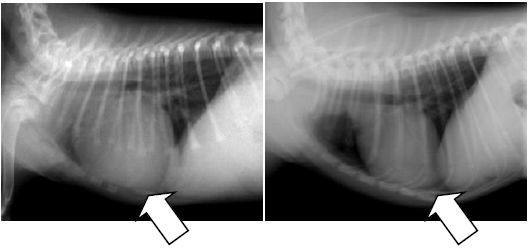

エコー、レントゲン、心電図、血圧測定など一通りの検査を行ったところ、動脈管開存症(どうみゃくかんかいぞんしょう)という心臓病が見つかりました。

この異常のせいで血液が上手く心臓から出て行かず、心臓に血液が溜まってパンパンになっていました。 このまま放置すると成長が悪くなるだけでなく、若くしてお別れとなる可能性が大だったため、ご相談の末、手術を行いました。 生後約2ヵ月と若く、体重も1kgちょっとの子だったため、ご家族も心配されていましたが、手術は無事成功し、元気に退院していきました。

手術前(左)と手術後(右)の胸のレントゲン写真を比べると一目瞭然ですが、心臓のサイズが正常に戻っています。